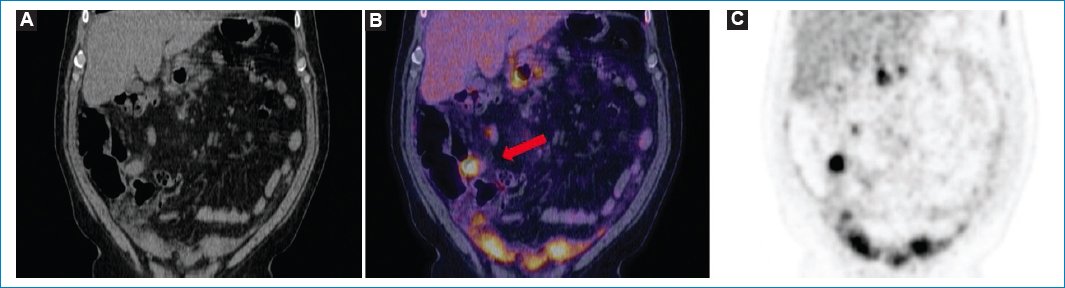

Figura 9. Paciente con diagnóstico de linfoma no Hodgkin e infiltración linfomatosa hipermetabólica difusa del peritoneo (flecha), evidente en las imágenes axiales de TC (A), MIP de PET (B) y fusión PET-TC (C).

Figura 10. Mujer de 49 años con diagnóstico de linfoma no Hodgkin agresivo (misma paciente de la figura 4), con progresión de su enfermedad y de la LP, con actual compromiso difuso del peritoneo (flecha roja), adenomegalias múltiples hipermetabólicas en diferentes niveles ganglionares (flecha azul) y compromiso óseo (flecha verde); hallazgos evidentes en los cortes coronales de TC (A), fusión PET-TC (B) y MIP (C y D).